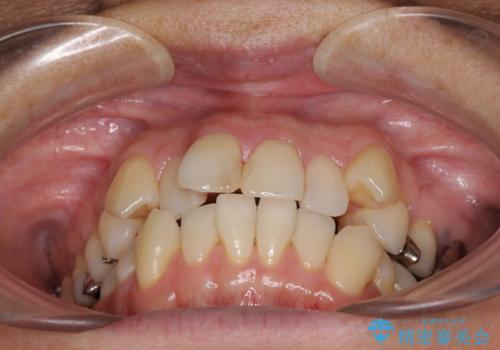

- 八重歯と、それによる口元の膨らみを気にして来院された患者様です。

八重歯・デコボコの解消とともに、前方に張り出した上顎前歯を引っ込めることを目的とし、上下左右の第一小臼歯4歯を抜歯をしてワイヤー矯正により治療することとしました。